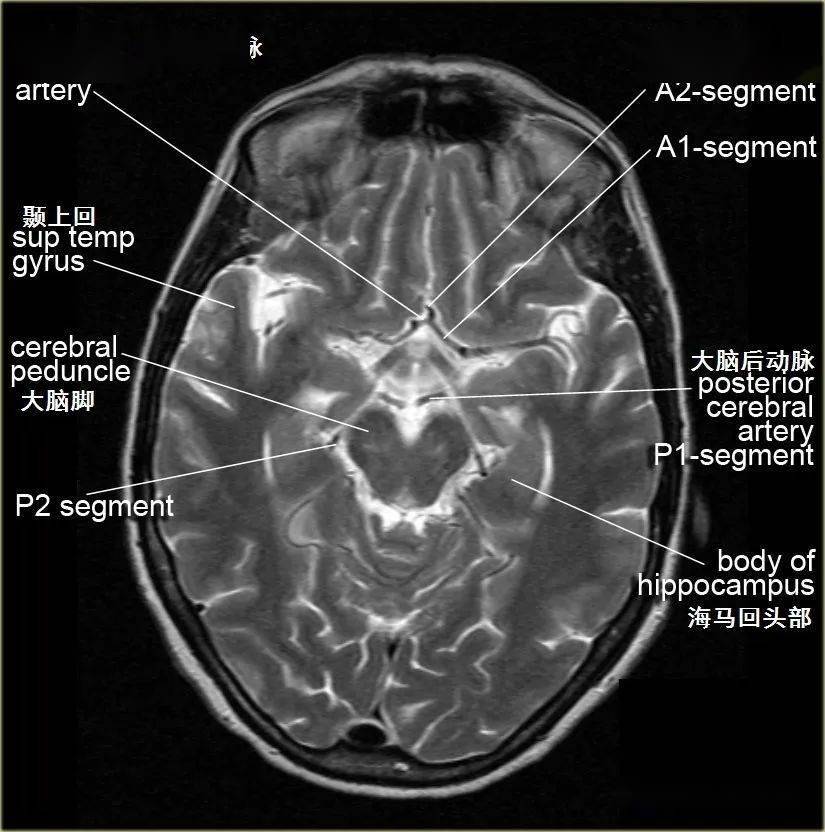

学习借鉴脑的断面解剖

图片尺寸825x832